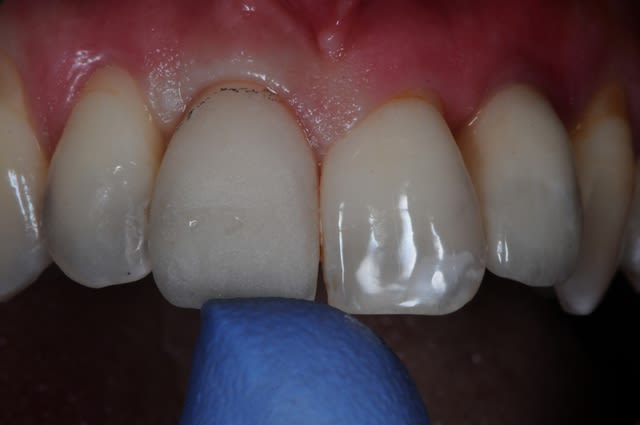

voici un cas qui aurait fort bien pu mal tourner.

j’étais prêt à déposer l'implant car je ne trouvais pas le résultat satisfaisant à j+20 jours.

finalement on a quand même gardé l'implant et l'ancienne couronne qui a servi de provisoire lors de l'EMCI.

vue la photo de la dent, je crois bien

12